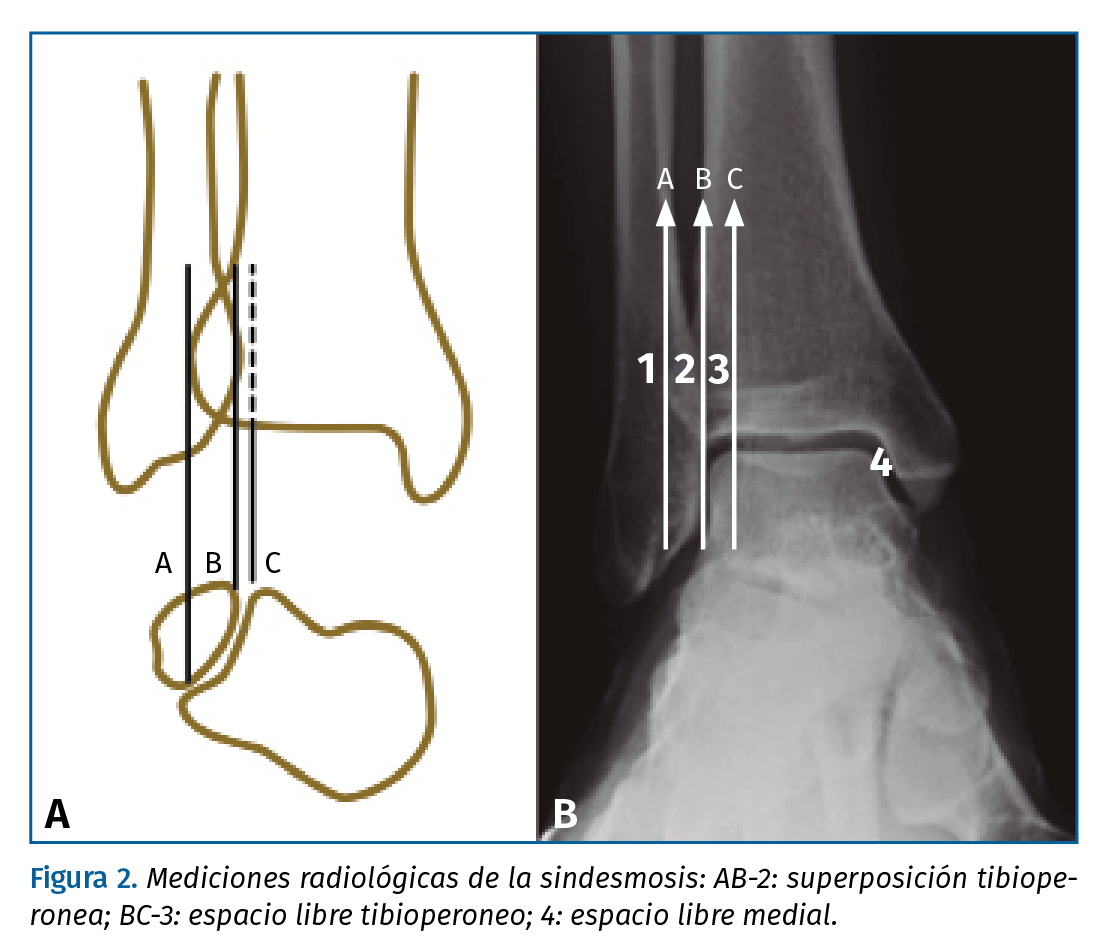

Una diástasis completa tibioperonea es fácil de identificar y nos pone de manifiesto una afectación de todas las estructuras ligamentosas que estabilizan la articulación. Pero la mayoría de las lesiones sindesmales no muestran una clara manifestación radiológica; por ello, debemos prestar especial atención al espacio libre medial, superposición tibioperonea y espacio libre tibioperoneo, descritos por Harper y Keller en 1989(17). El valor fuera de los límites considerados normales de alguna de estas mediciones debe hacer sospechar una afectación sindesmal, pero la normalidad de los mismos no nos descarta el diagnóstico.

El espacio libre medial es el comprendido entre el borde medial del astrágalo y el borde lateral de maléolo interno, y se considera normal si la distancia entre la cúpula astragalina y la tibia es menor o igual a 4 mm; mediciones superiores manifiestan una traslación externa del astrágalo dentro de la mortaja, posible por una apertura sindesmal y lesión del ligamento deltoideo(18).

El espacio libre tibioperoneo normal, comprendido entre el borde lateral del tubérculo posterior de la tibia y el borde medial del maléolo peroneo, a 1 cm de la carilla articular tibial, es menor a 6 mm.

Por último, un valor mayor de 6 mm en la proyección anteroposterior o mayor de 1 mm en la proyección de mortaja se considera normal respecto a la superposición tibioperonea(3)(9)(10)(13)(14)(17) (Figura 2).

Figura 2. Mediciones radiológicas de la sindesmosis: AB-2: superposición tibioperonea; BC-3: espacio libre tibioperoneo; 4: espacio libre medial.